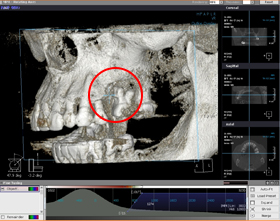

歯周病

デジタルXray写真(2次元)

CT 3D画像

3枚の写真、赤丸部分が歯周病により歯の周りの骨が吸収しているのが認められます。

CT画像(3次元)